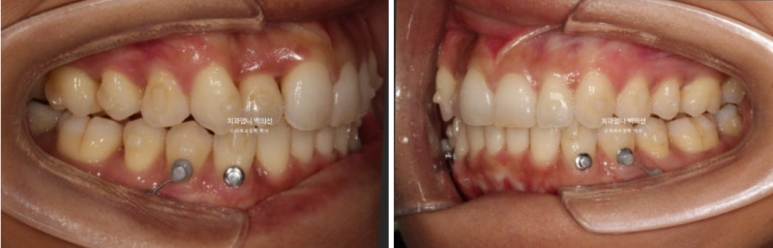

23년 9월 교정치료를 이해 내원하신 분입니다.

고치고 싶은 것은 3가지 입니다.

덧니, 비대칭, 입이 잘 안다물어지는 것

위 아래 앞니 중심선 불일치가 보입니다.

엑스레이를 찍어보면 뼈의 비대칭은 없으나 덧니때문에 위 앞니 중심선이 한쪽으로 쏠려서 비대칭감을 느끼는 상태입니다.

입천장으로 들어가있는 측절치는 아랫니와 반대로 물리는 반대교합 입니다.

덧니가 심하고 입이 잘 안다물어 지기는 하지만 입매 분석시 입술 돌출이 없어서 작은어금니 발치는 하지 않았습니다.

대신 사랑니 공간이 충분해서 사랑니 공간으로 어금니 후방이동을 통해 덧니를 배열하기로 합니다.

어금니 후방이동에 교정용 나사인 미니스크류는 꼭 필요합니다.

멀리서 오시기에 내원간격 때문에 인비절라인 치료를 선택하셨고 23년 10월부터 24년 8월까지 첫세트 44개 장치를 모두 낀 후 모습입니다